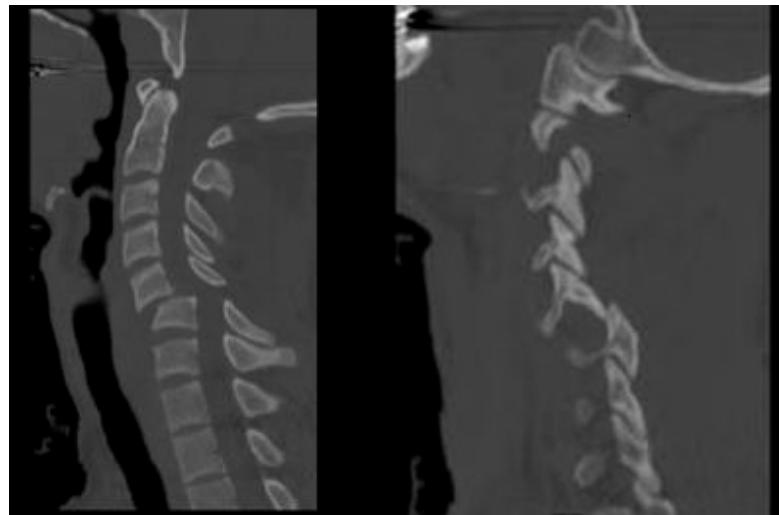

C2 Odontoid Fractures

- Seen in: Low-energy falls in elderly patients and high energy traumatic injuries in younger patients

- Diagnosis: Standard lateral and open-mouth odontoid radiographs; CT scan for difficult cases

- MRI: Rarely indicated as these fractures are usually not associated with neurologic symptoms

- Treatment: Nonoperative or operative depending on type and risk factors for nonunion

Cervical Facet Dislocations

- Spectrum of traumatic injuries with varying degrees of cervical instability and risk of spinal cord injury

- Diagnosis: Confirmed with radiographs or CT scan

- MRI: Should be performed before surgery to identify associated disk herniation

- Treatment: Closed or open reduction, followed by surgical stabilization